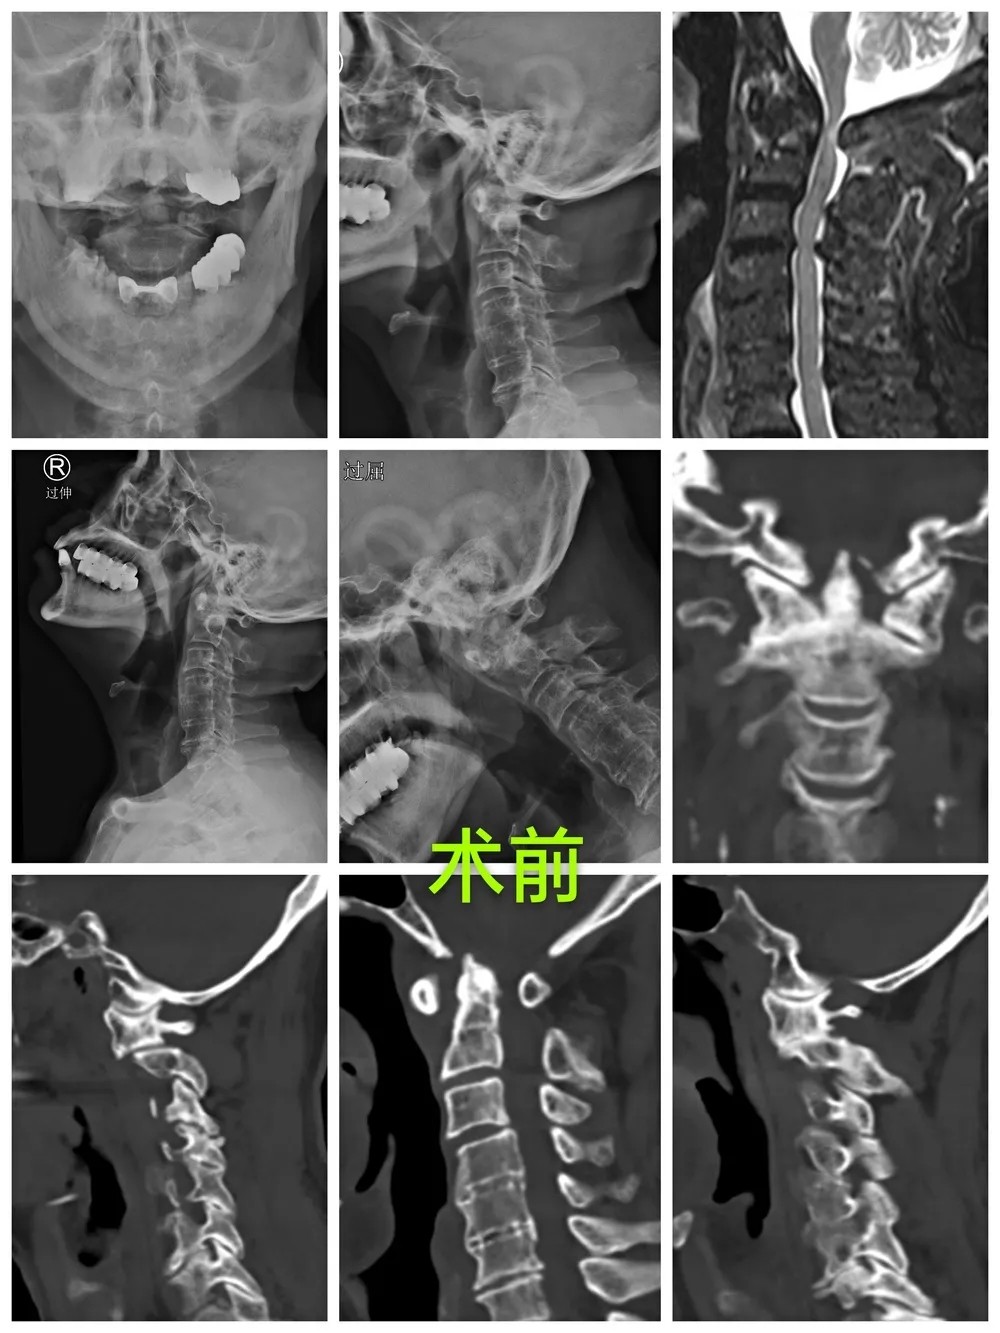

After taking a careful consideration into his medical history, physical examination and the imaging results, Prof. Lin confirmed his diagnosis that the patient had several cervical vertebra problems, including atlantoaxial dislocation, upper cervical myelopathy and high-riding left vertebral artery, so he recommended that a surgery should be performed as soon as possible. When it came to design the operative plan, there were two factors that need to be considered. One was that the patient is already 80 years old, and the other was that he had high-riding left vertebral artery with the vertebral artery dominance, which may result in a higher risk of vascular injury if a screw is used, and may further cause serious complications such as cerebral infarction or even death after surgery. After considerable discussion, the team of Prof. Lin decided to perform the surgery by following three steps: firstly, performing gradually great weight skull traction for positioning the dislocated cervical vertebra under general anesthesia; secondly, precisely inserting the screws with the help of “Tianji” surgical robot; thirdly, decompressing under 3D microscope that enables a high-definition visualization of the process.

The surgery lasted for less than 90 minutes and the peri-operative blood loss was about 70ml. During the surgery, the screws were well distributed so that the relocation of the atlanto-axial joint, and the decompression were all fully realized. The patient's symptoms were greatly relieved and his neck pain disappeared completely after the surgery, and the patient could walk freely with the neck brace on the first day after the surgery. He said gratefully with his thumbs up to Prof. Lin, "I haven't had such a good sleep for a long time, thank you very much!"

Prof. Lin pointed out that the upper cervical vertebra surgery is regarded as the "the Pearl of the crown" among other kinds of spinal surgeries due to its strict surgical requirements, for example, the demand to handle emergencies, to face a higher risk of multiple complications and vascular malformation(like high-riding vertebral artery) and a lower accuracy rate of screw placement. In China, there are only a few spinal experts in top hospitals that could perform this challenging surgery. Luckily, with the support of the “Tianji” surgical robot and 3D microscope, three “weapons” - a careful preoperative planning based on 3D imaging, a precise intraoperative positioning of the screws and a high-definition visualization of decompression process - could be achieved and have made many difficult, highly-risky and complicated spinal surgeries performed in an easier, safer, more efficient and more intelligent, and even more minimally invasive way.